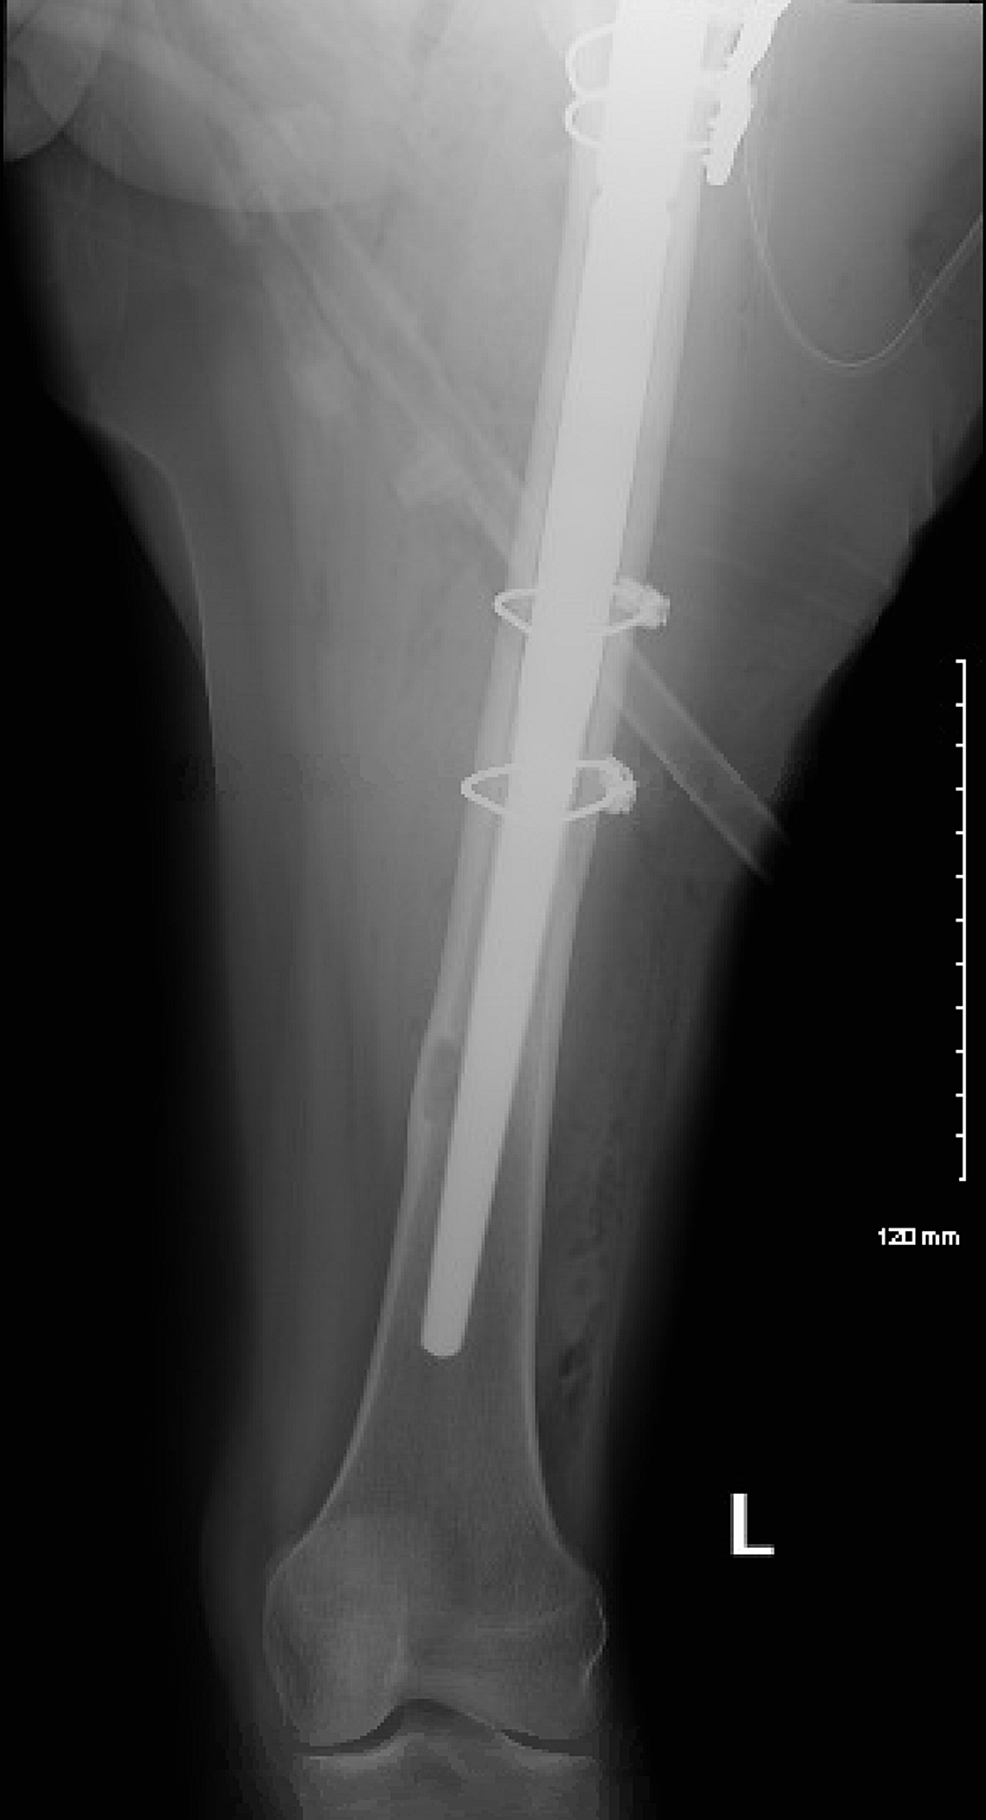

IM Rod Femur What Is A Prophylactic Fixation Several methods exist to predict the risk of pathologic fracture. Prophylactic fixation refers to operating on an impending pathologic fracture before it occurs to. prophylactic surgical stabilization is often recommended to prevent fracture rather than waiting for the. the aim is to evaluate and to highlight on value of prophylactic fixation of impending fractures in abnormal bone. . What Is A Prophylactic Fixation.